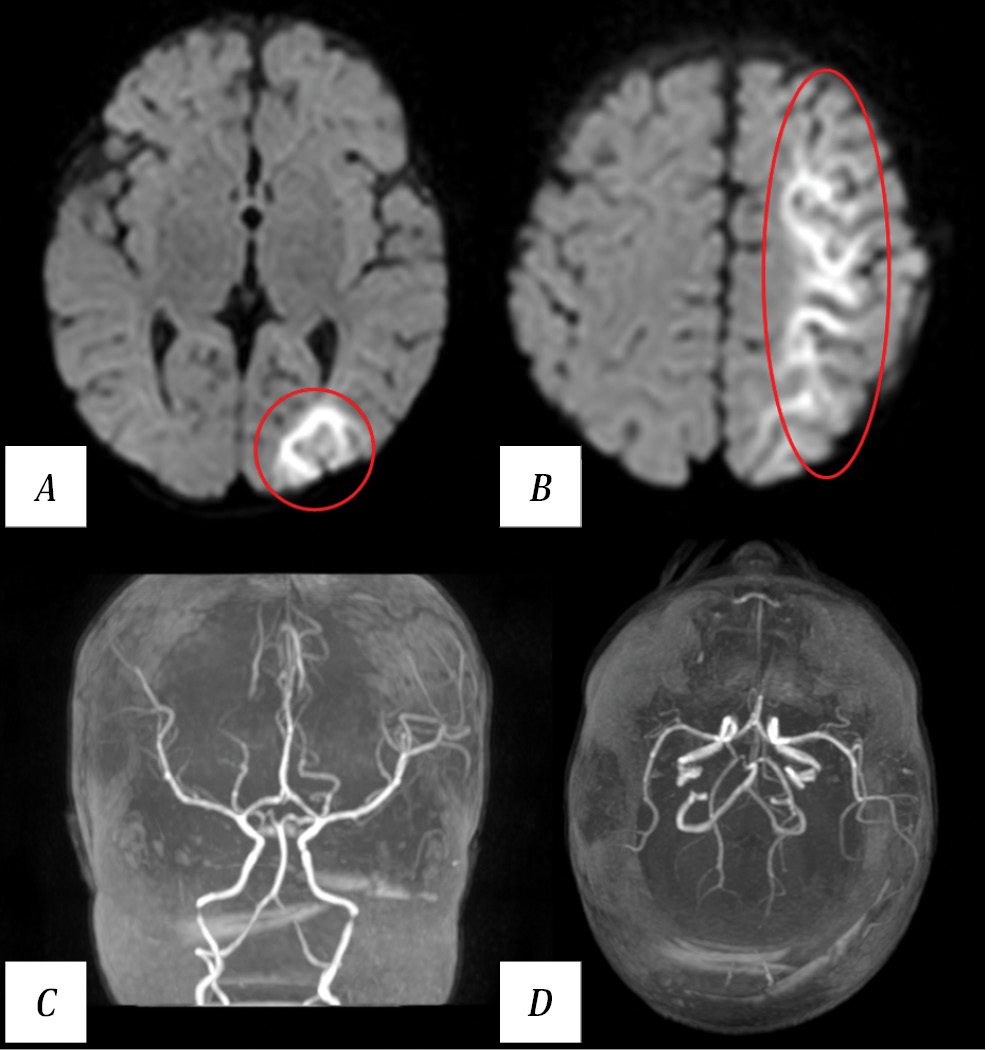

Brain magnetic resonance imaging (MRI) revealed a watershed infarction in the left hemisphere (Fig. 2), while 3D time-of-flight (TOF) MR angiography showed no signal changes in the intracranial arteries.

Fig. 2. Results of patient T. MRI on day 2 postoperatively.

A, B — brain MRI. Diffusion-weighted imaging (DWI), axial view. MRI findings of a watershed infarction in the left hemisphere (within the red oval). C, D — MR angiography, 3D reconstruction. Blood flow in the intracranial arteries of the head is intact.